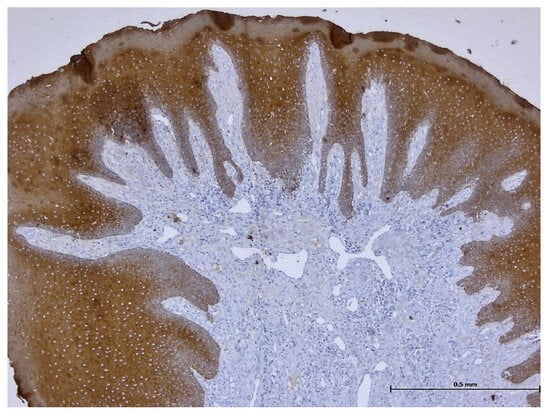

A Retrospective Histological Study on Palatal and Gingival Mucosa Changes during a Rapid Palatal Expansion Procedure

3. Results

| AE1/AE3/PCK26 | Anti-Pan Keratin primary antibody |